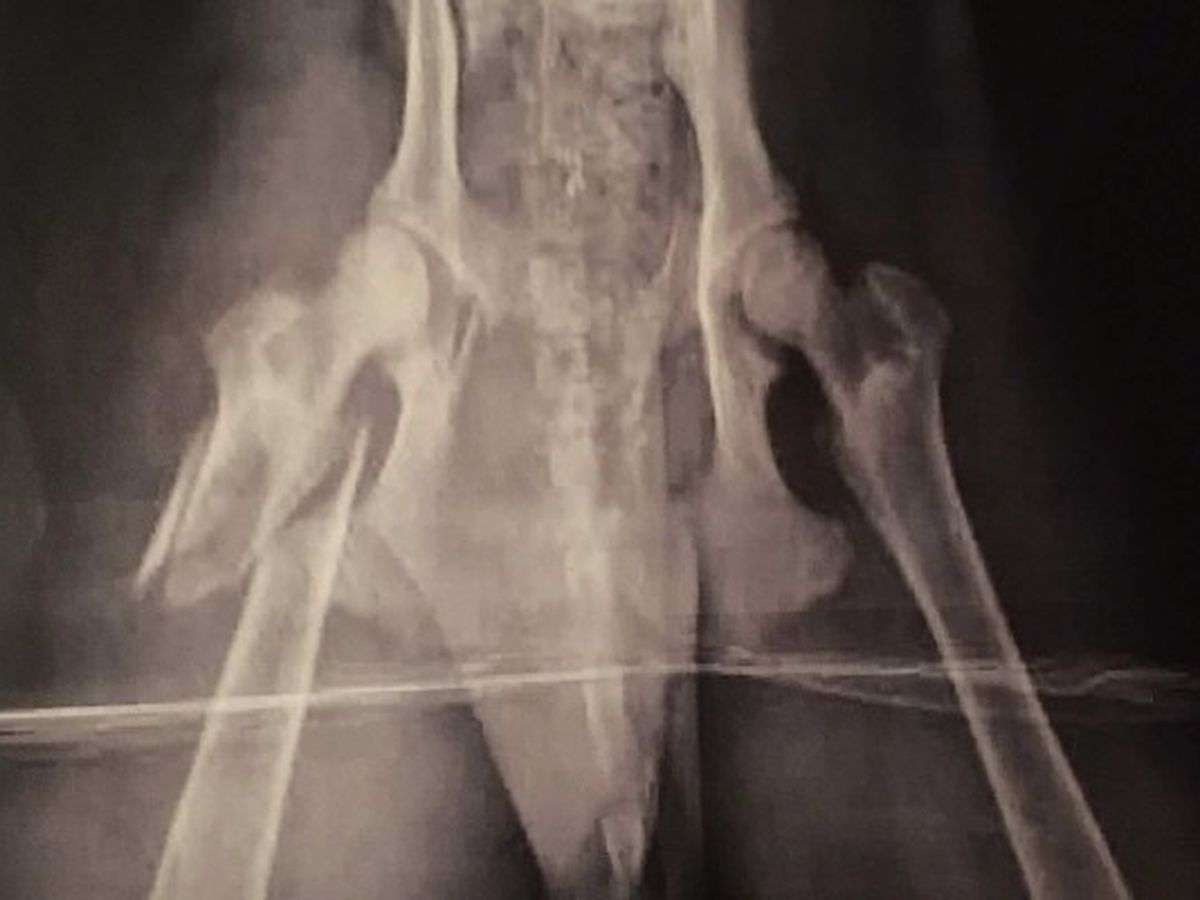

Magic is from the Stockton Animal Shelter and needs surgery to fix her shattered femur. She is very sweet and likes other dogs despite her injury.